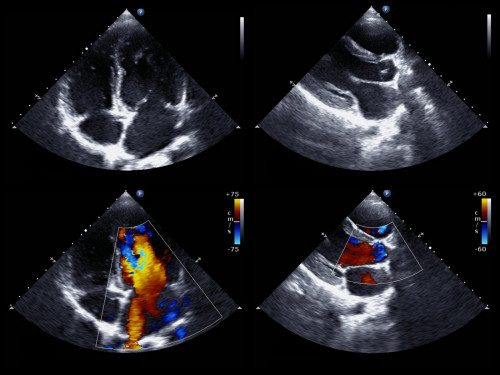

Эхокардиография (ЭхоКГ)

Ультразвуковое исследование сердца в режме он-лайн.

В наше время только ЭхоКГ может быть критерием патологии клапанов сердца. Любые разговоры о пороках (врожденных или приобретенных) без ЭхоКГ бессмысленны.

При ЭхоКГ видны последствия перенесенных/переносимых инфарктов - в виде нарушения соратимости стенок сердца и это может являться критерием.

Метод достаточно сильно зависим от квалификации оператора (врача ФД) и от качества аппаратуры.

К сожалению, до сих пор рутинно нет технической возможности записывать видео всего исследования, поэтому иногда приходится пересматривать ЭхоКГ повторно с консультантом.

Для более подробного изучения некоторых структур сердца ЭхоКГ может выполняться специальным датчиком из пищевода (ЧПЭхоКГ).